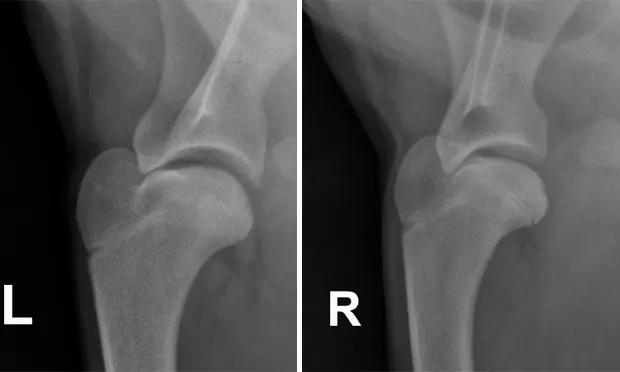

Shoulder Radiographs: Lateral views of both the left and right (Figures above) shoulders were performed. Craniocaudal views were also obtained (not shown).

Figures above. Lateral views of the left and right shoulders.

Radiographic Findings: Subtle subchondral lucencies were identified along the caudal margin of both humeral heads, supporting osteochondrosis (OCD). No panosteitis or other abnormalities are detected.

Figures 2A and 2B. Same images as Figures 1A and 1B, but with arrows pointing to the subchondral defects._